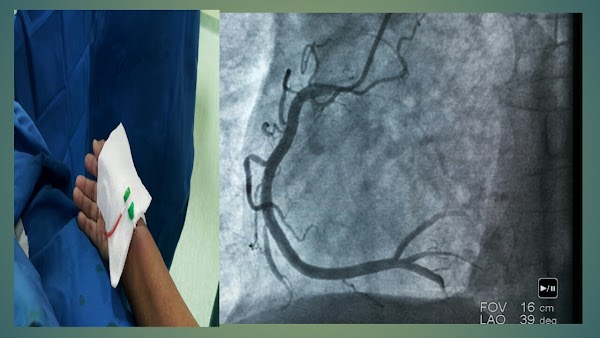

Angiorafi koroner merupakan suatu tindakan diagnostik invasif yang bertujuan untuk melihat gambaran aliran darah dalam pembuluh darah arteri jantung (arteri coroner) dengan menggunakan contras dan sinar-x.

Dengan dilakukan tindakan ini akan ketahuan ada tidaknya penyumbatan pada lumen penbuluh darah coroner.

| Gambaran RCA dari angiografi |

Tindakan angiografi coroner ini dilakukan untuk mendapatkan gambaran pencitraan dari pembuluh darah coroner khususnya mendeteksi adanya penyempitan atau penyumbatan didalam pembuluh darah koroner.

- Radialis, alat dimasukkan ke jantung melalui arteri radialis pada pergelangan tangan biasanya lengan sebelah kanan.

- Femoralis, alat dimasukkan ke jantung memalui arteri Femoral pada selangkangan dan biasanya juga sebelah kanan.

Pasien ditidurkan di C-Arm dengan posisi terlentang, setelah di pasang chest lead untuk memantau hemodinamik selama tindakan, area puncture ( di lengan kanan atau femoral kanan) di disinfektan, kemudian di tutup dengan linen steril supaya area kerja tetap steril.

Angiographic Chateter dimasukkan melalui lengan kanan atau Femoral kanan dengan wire penuntun mengikuti lumen pembuluh darah arteri hingga melewati Arcus Aorta dan mengarah ke sinus coronarius (muara dari pembuluh arteri jantung) kemudian dokter akan menyemprotkan kontras melalui alat angiography chateter sambil direkam dengan alat x-ray sehinggan aliran kantras terlihat di pembuluh darah arteri koroner. Selama tindakan tindakan pasien di bius lokal.